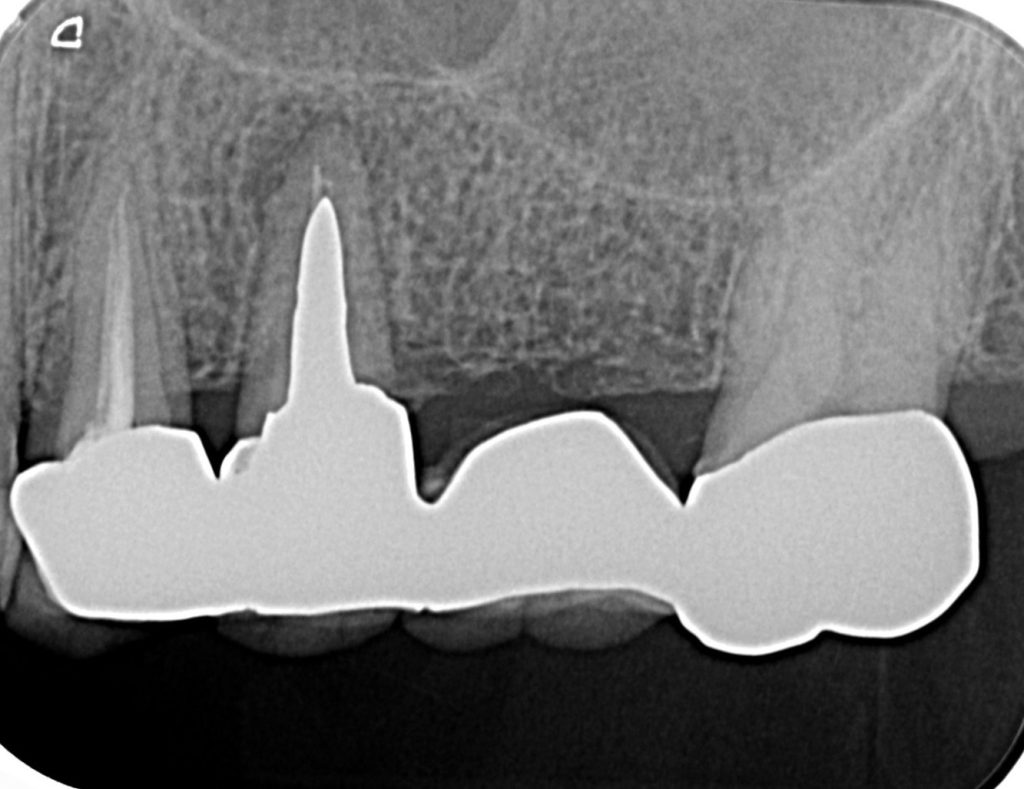

50代、男性、左上に違和感があることを主訴に来院され、インプラント治療を行いました。

| 診断結果 | 左上5番歯根破折 |

| 治療内容 | 抜歯即時インプラント |